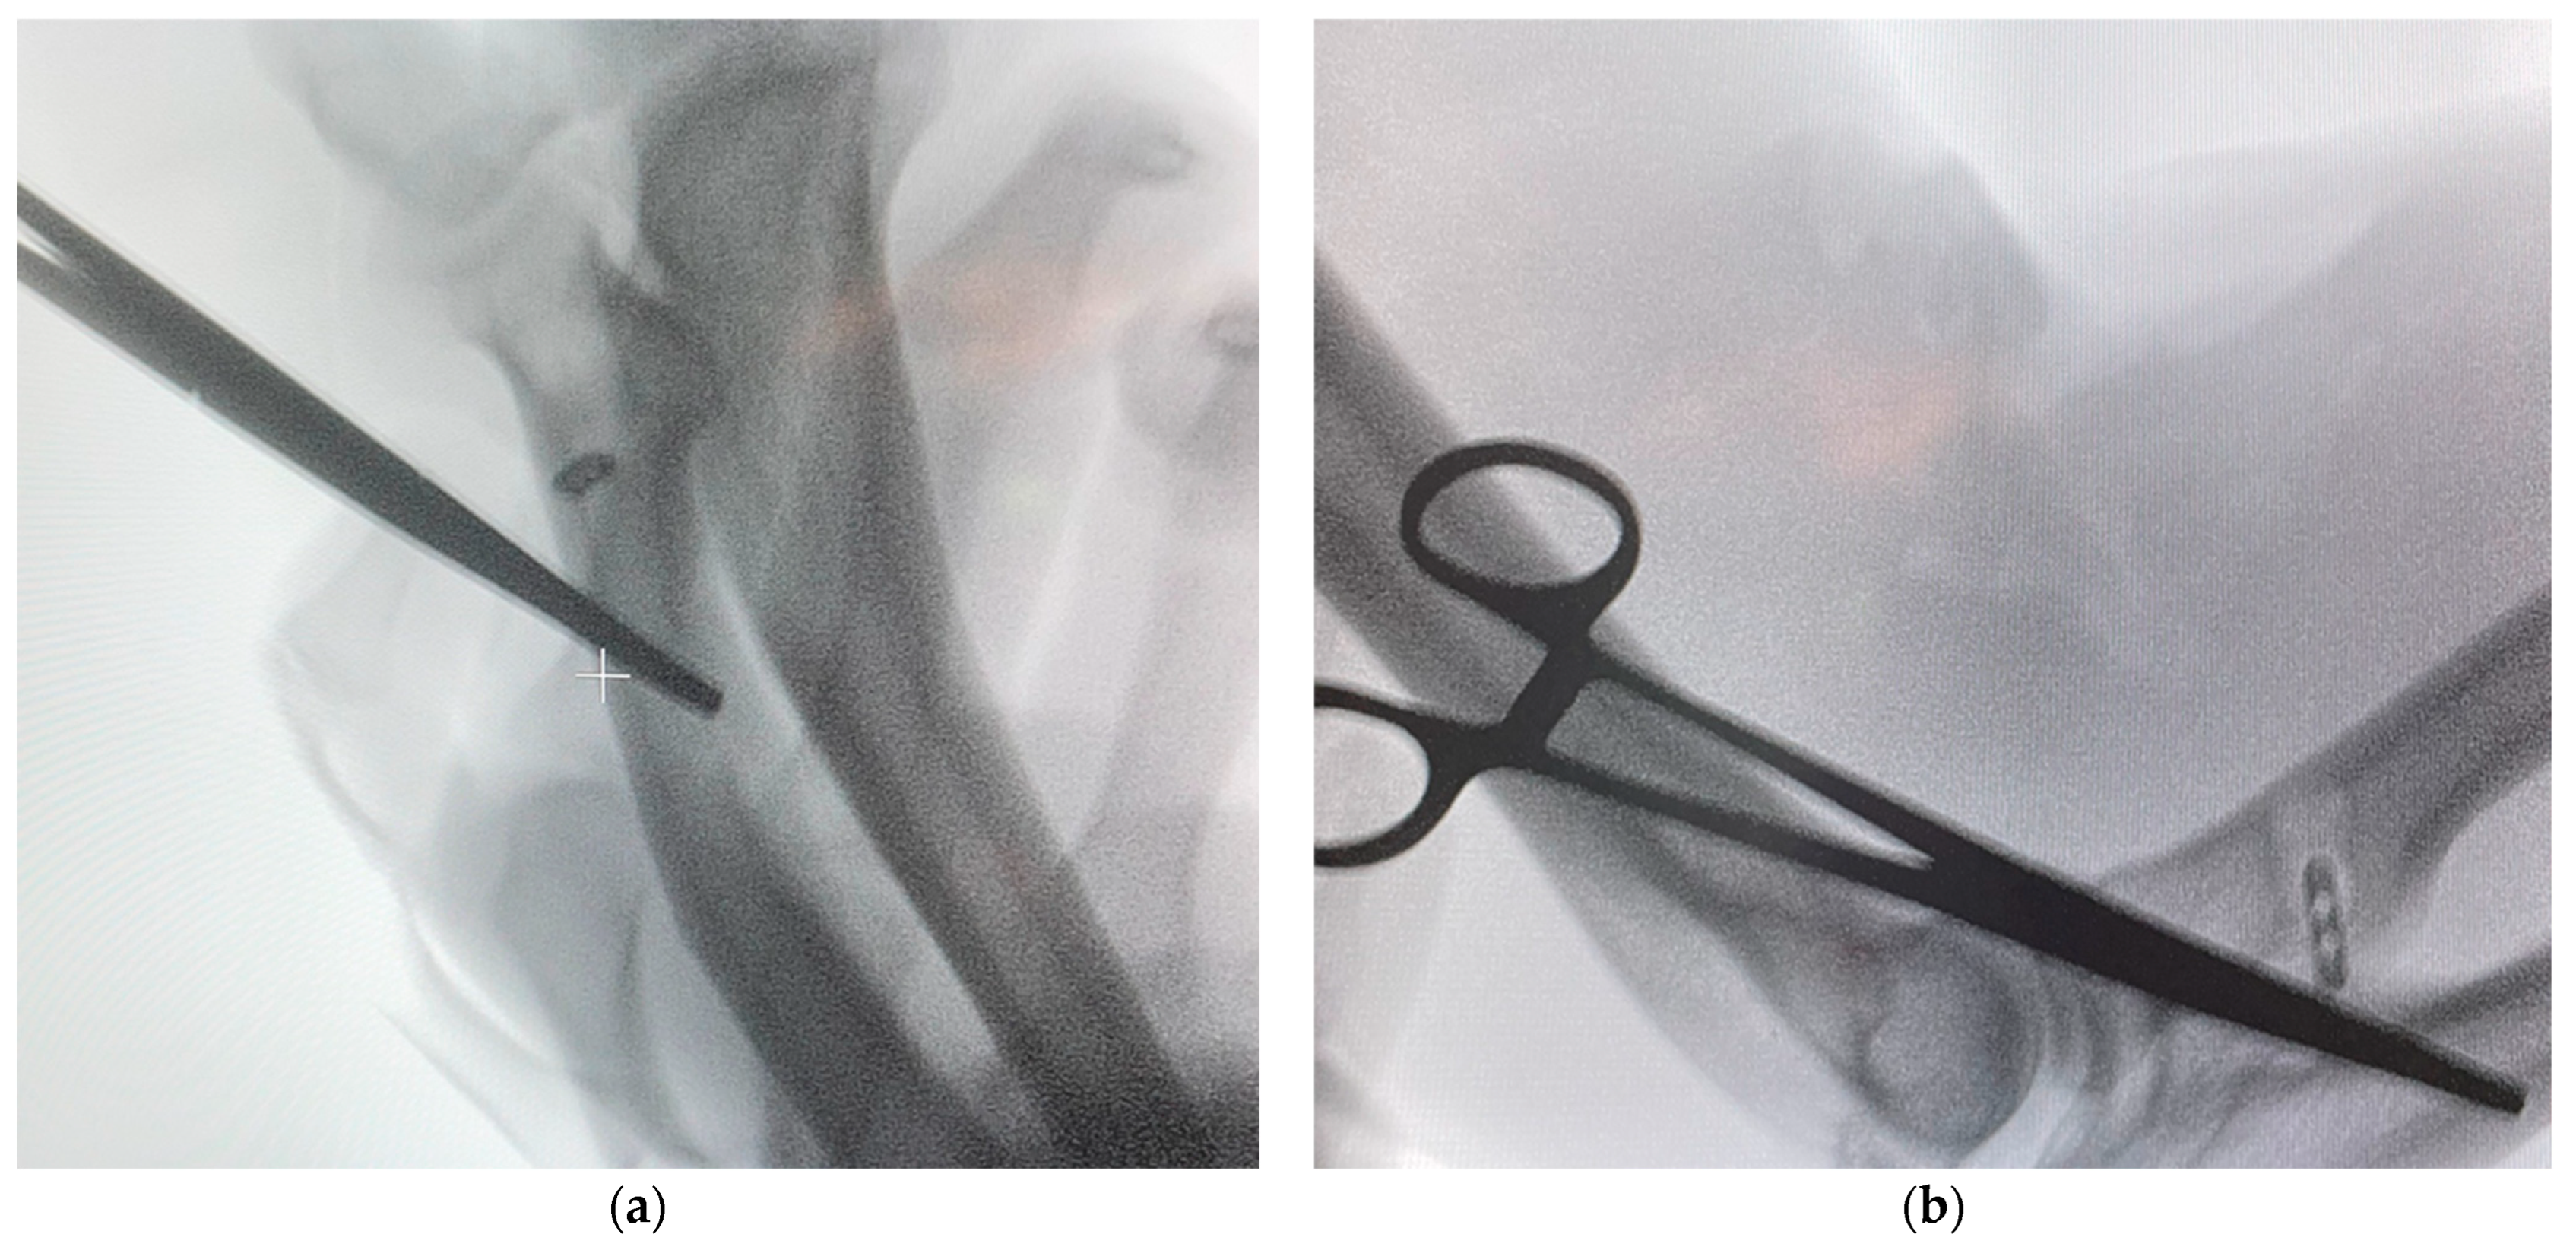

2.4.5. Intraoperative Evaluation

3.1. Intraoperative Findings and Fixation Stability